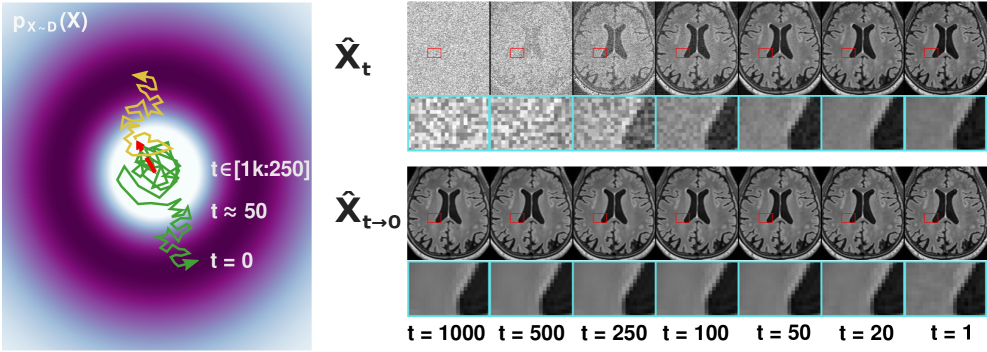

(a,b) Exemplary MIT and NIG image density functions are projected for visualization. (a) The noisy image acquisition and the strong condition required for faithful MIT (e.g., T1w,T2w FLAIR) creates a uni-modal cluster of acquirable noisy images centered around the noise-free image . (b) Conversely, the complex image formation and typically weak condition in NIG (e.g., CIFAR-10 [53] class conditional) leads to a density landscape with scattered and distinctive modes (compare also Fig. 3 in [6]).

(c + d) Sampling trajectories and exemplary outputs of ideal MIT (c) and NIG (d) denoisers (see also [5, 54]). (c) Note that the generated MIT samples share the medical information (e.g., lesions) but differ in the noise manifestations (best viewed zoomed in). Thus, image averages are valid () images. (d) Conversely, NIG sampling branches into distinctive objects of the class (e.g., ”airplane”) [5, 54], such that averages are predominantly invalid () images.

(e) Proposed Expectation-Approximation (ExpA) Sampling (Samp.): Similar to physical signal averages, uncorrelated noise in samples drawn from enables noise suppression by averaging . For an ideal , averaging many samples slowly approaches (see also the supplementary video).

(f) Proposed Regression Sampling (Regr.): We simply use the initial minimum-mean-squared-error (MMSE) solution, , without further refinement and, thus, noise generation to directly approximate .

(g) Whereas ExpA requires full DDPM sampling and exacerbates the intrinsically high number of function evaluations () of DDPMs, regression sampling leverages the single-step MMSE solution requiring only . Note that ExpA and regression sampling both approximate the superposition of all valid objects given . While in NIG, this is meaningless [6, 54], the strong conditioning and, thus, semantic determinism of MIT make this superposition well-defined with a correspondence to the noise-free image .

As the initial solution remains practically unchanged for many late diffusion steps (Fig. 3), we truncate DM sampling: we skip the following low-SNR denoising steps, i.e. we only consider by setting in the modified Alg. 3. Note that in contrast to CMDM [34] and MADM [35], we derive the truncation directly from the backward process, re-using the initial DM solution, , as the prior.

The theoretical minimum of this objective is assumed at the MMSE solution, i.e. and, thus, a perfect DM would already predict noise-free images in the first sampling operation (Fig. 1e). This provides a tractable alternative to sampling the DM with (Fig. 1f). We therefore also considered this initial solution of YODA as a sampling method for approximating noise-free images, i.e. .

As this sampling only uses the regressive single-shot abilities of the DM and is expected to have the same image properties as applying dedicated RMs, we term this regression sampling ( in Alg. 3).